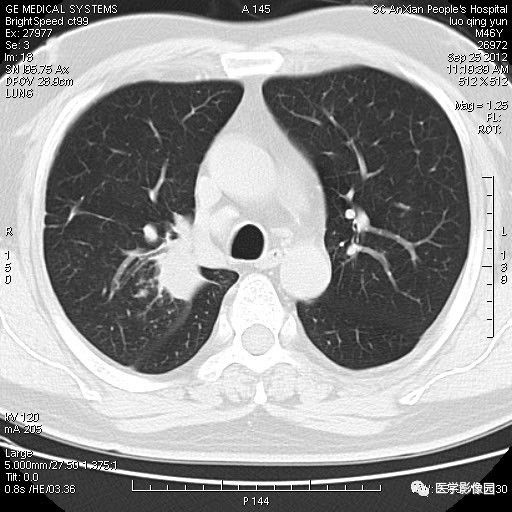

【病例】右上肺炎性假瘤1例CT影像表现

患者男性,46岁,临床未提供病史。

影像学表现:右上肺见不规则团块状高密度阴影,略有分叶级毛刺,边缘模糊,邻近胸膜增厚,增强扫描呈轻中度强化。

诊断结果:右上肺炎性假瘤

本病影像学表现无绝对特征性。单发多见,多位于肺表浅部位,多呈圆形或椭圆形,直径多在2-5cm或更大;多有假包膜,边缘多清晰光整,有时也毛糙,并可有分叶或毛刺;邻近胸膜局限性增厚、牵拉,病灶边缘呈桃尖样突起即桃尖征(尖端指向胸膜);增强扫描多呈中度均匀强化,持续时间较长。亦可显著强化。